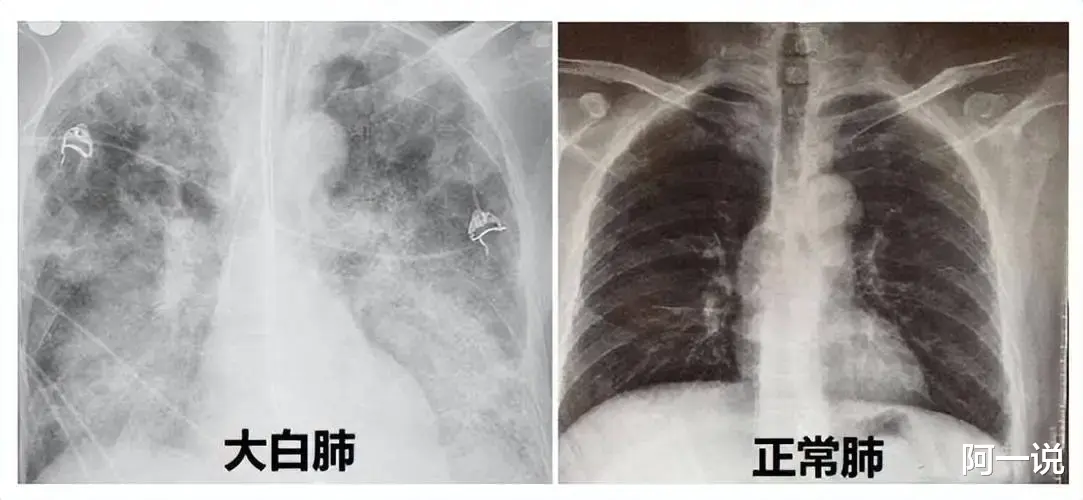

最近 , 因为新冠感染引起的白肺引发了很多民众的担心与讨论 , 对此 , 专家作出了回应:

白肺会导致氧气不能通过肺泡进入气血屏障、进行气血交换 , 人离开了氧气就会威胁生命 。 白肺是一种“欺软怕硬”的疾病 , 免疫功能正常的情况下 , 绝大多数人很难出现白肺 。 因此 , 如果在流感季节出现咳嗽等呼吸道不适的症状 , 要注意休息 , 调整饮食 , 让自己尽快恢复 。 如果3-5天后出现高热 , 且症状越来越重就要及时就诊 。

最近 , 人们都谈“白”色变!需要提醒的是 , 白肺病是内科常见病 , 不是新冠病毒爆发后才产生的 , 也不是感染新冠后一定会发生的 。 经常吸烟的人也容易得 。 但是要是把民众苦难拿来娱乐化 , 确实就非常不合适了 。

大家必须要重视白肺的危害 , 阳康中和阳康后的 , 出现乏力气短、睡眠质量差的 , 咳嗽多 , 嘴唇发紫 , 长时间不愈等症状也应该先到医院拍一个胸片检查一下 , 不管年轻还是年老 , 长时间发热和咳嗽不停 , 呼吸不畅 , 血氧浓度低于93%就应该及时就医!